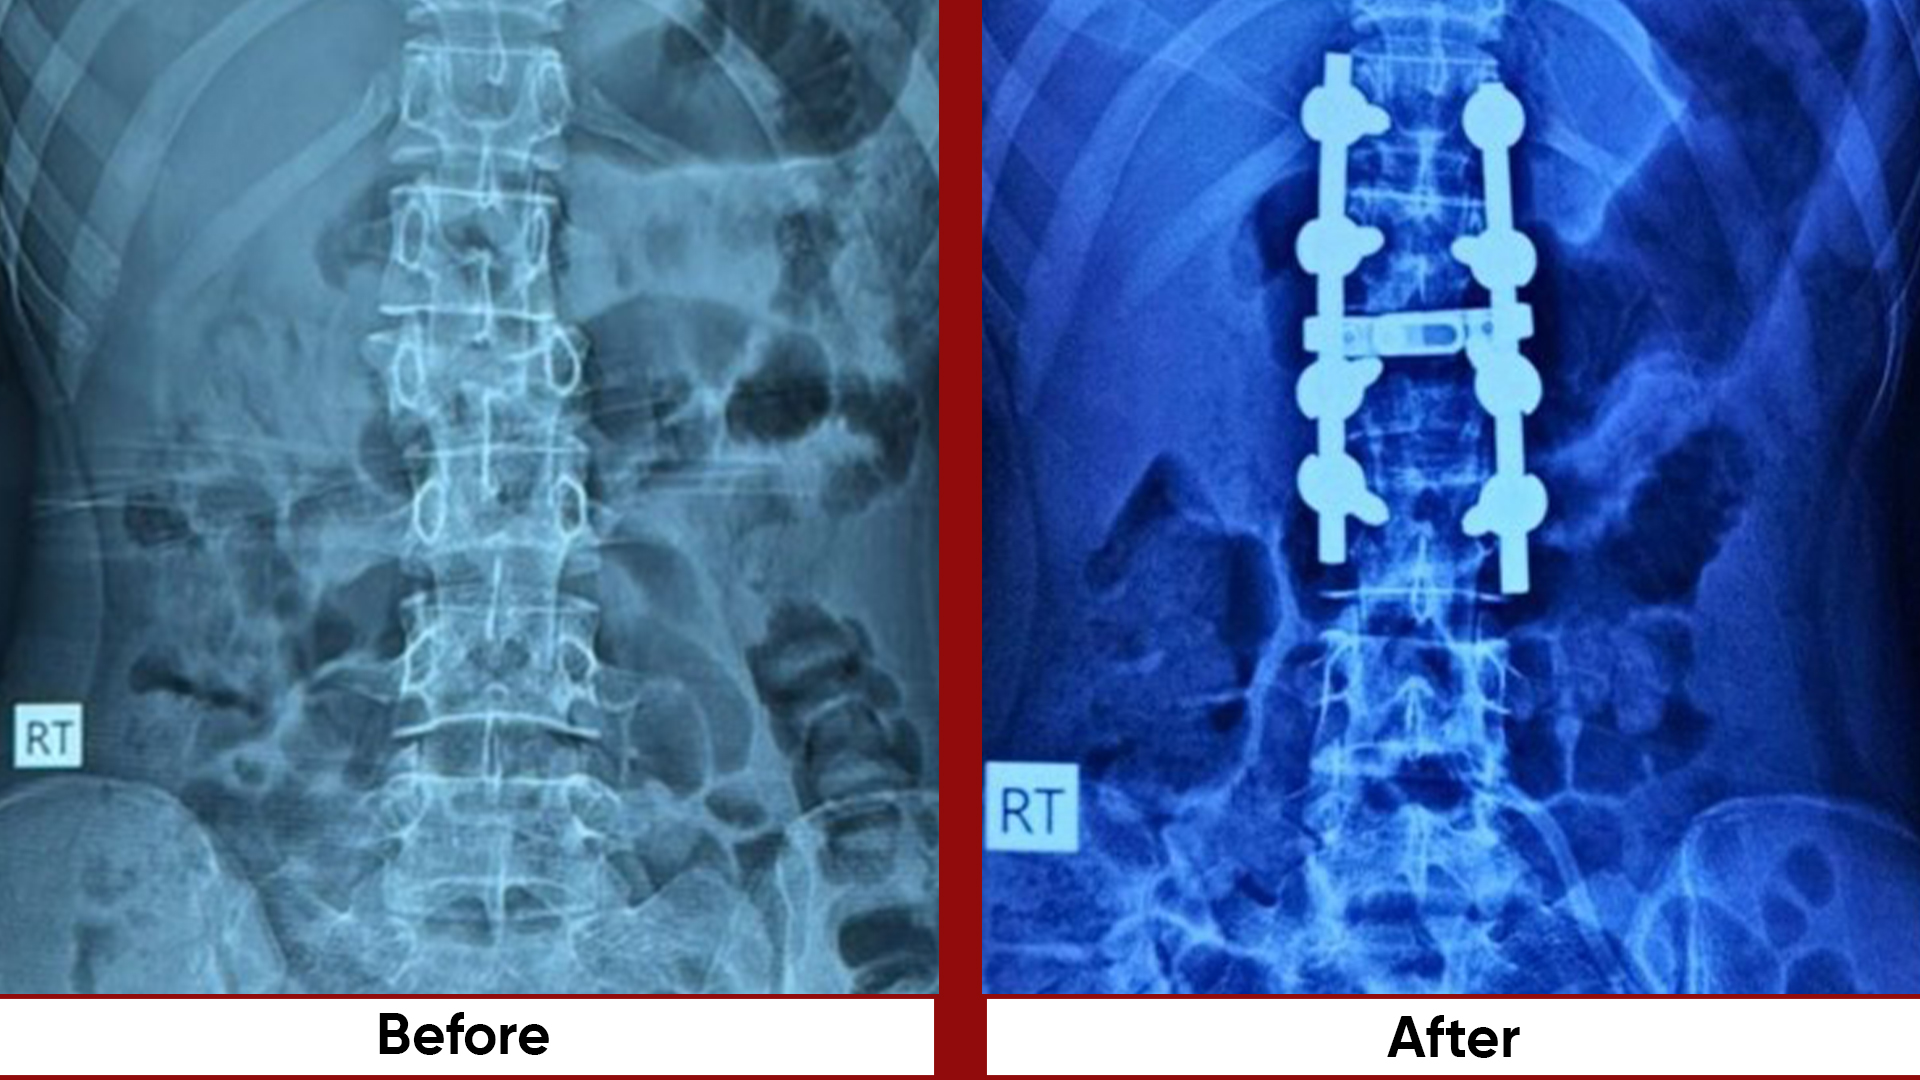

• Spine: Trauma Deformity –EOS AIS-Adult deformity, all fractures operated within 24/7.